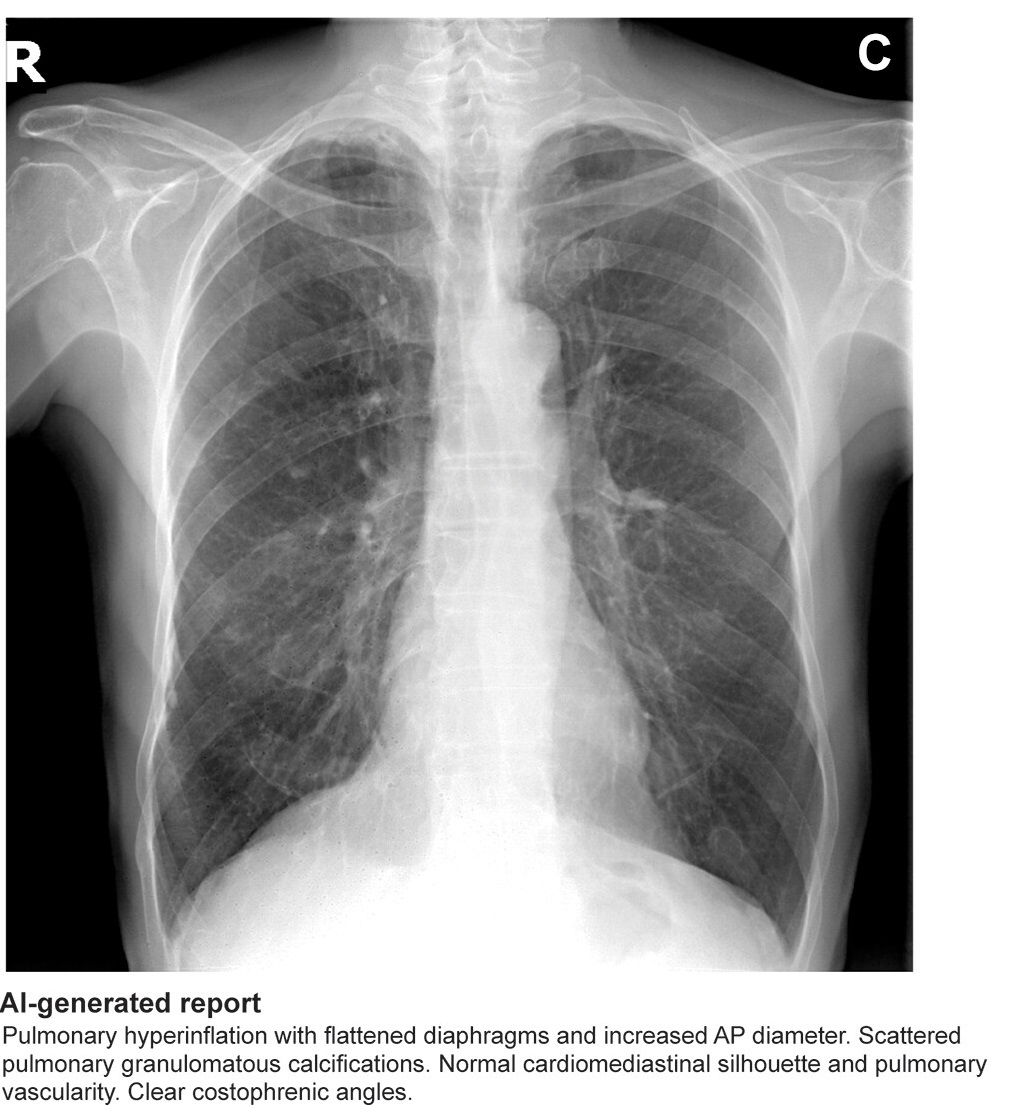

Established tests for achalasia include high-resolution manometry, esophagogastroduodenoscopy, and barium swallow tests. Alternatively, plain chest x-rays can capture several characteristic signs of the condition, such as air-fluid level, opacity, and air esophagogram around the mediastinum, the researchers noted.

To explore whether an AI model could be a useful screening tool for the condition, the group trained a deep-learning AI model using 207 chest x-rays from 144 patients with esophageal achalasia and 240 chest x-rays from age- and sex-matched individuals without it. The diagnostic capability of the AI model was then verified using a test dataset consisting of 17 chest x-rays from 17 patients with esophageal achalasia and 64 chest x-rays from patients without.

Saliency maps using Grad-CAM++ (E and H) show the model’s point of interest in chest radiographs (C and F) of patients with achalasia. The model’s point of interest is highlighted with red, yellow, and green. In both the upper and lower panels (E and H), the point of interest is located in a region around the upper esophagus that corresponds to an air esophagogram and/or air-fluid level in the esophagus in the barium esophagogram (D and G). Osaka Metropolitan University. Image available for republishing under Creative Commons license (CC BY-NC-ND 4.0)